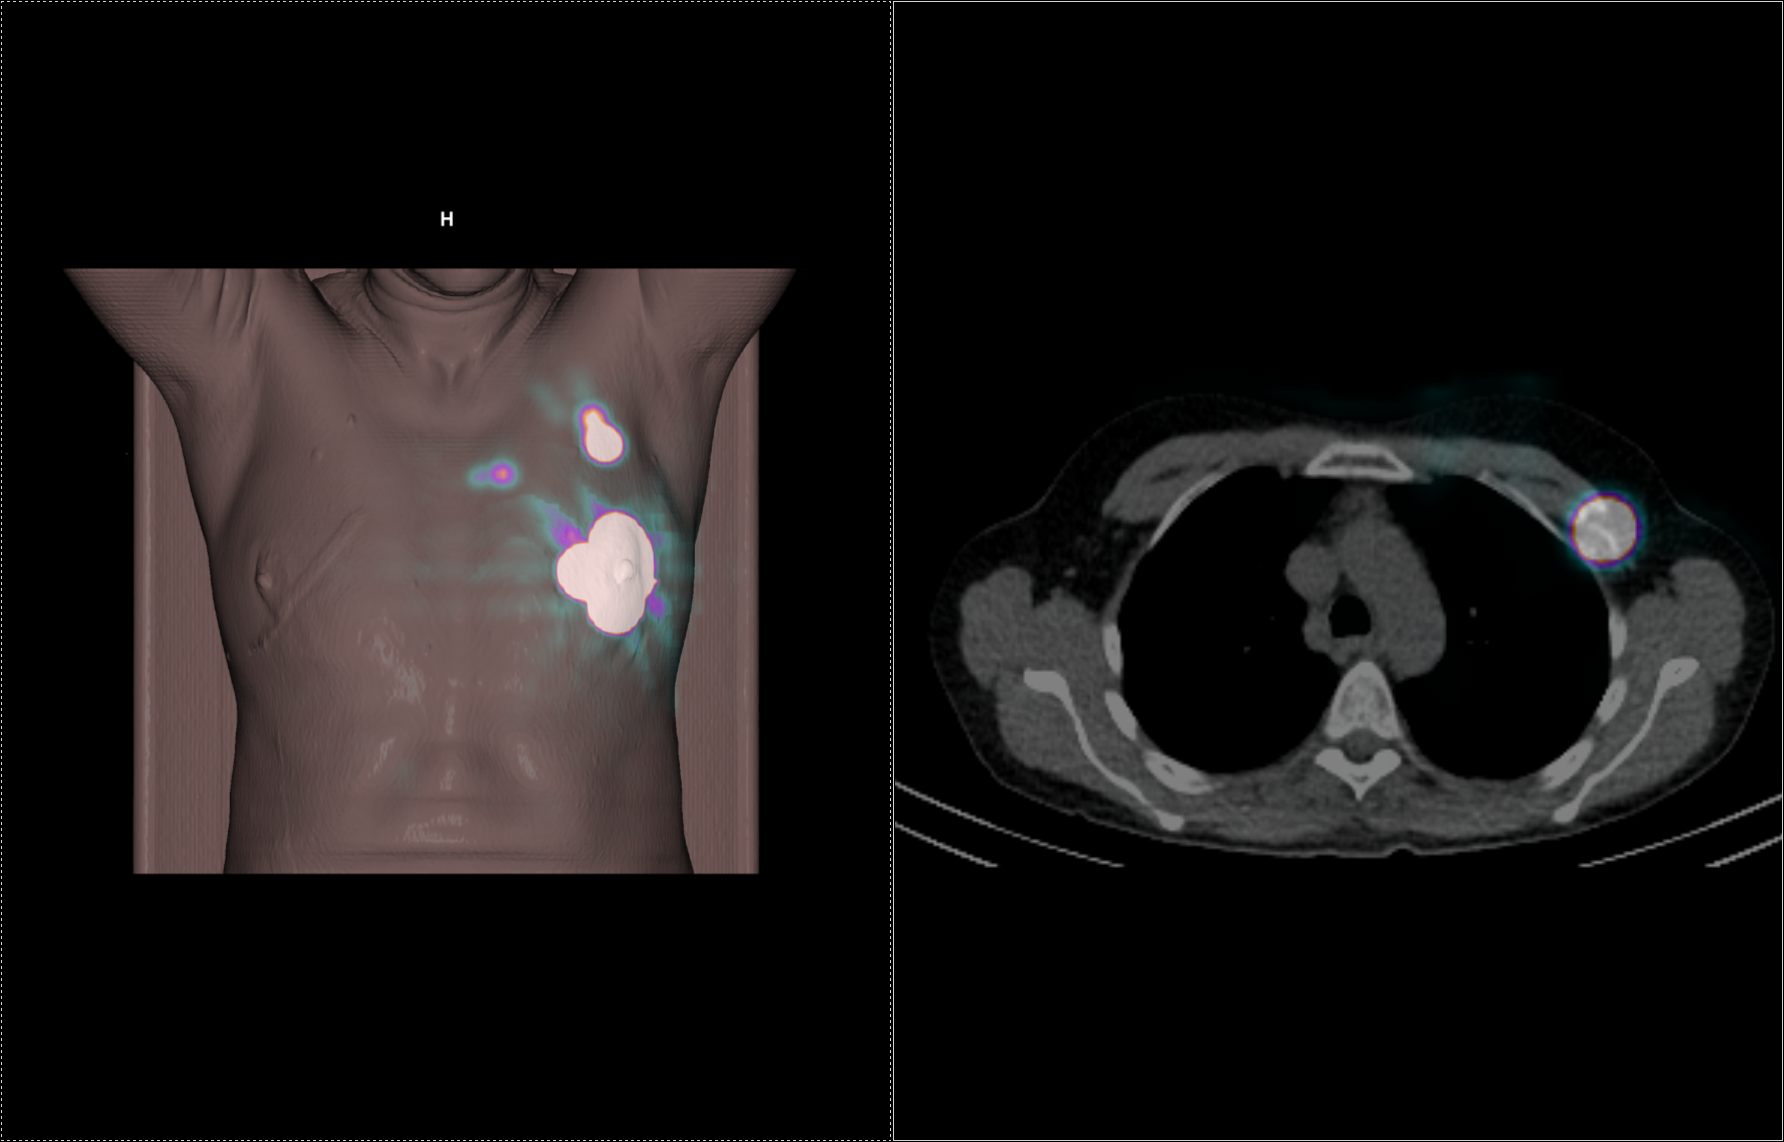

Το Lu-177 PSMA αποτελεί μια στοχευμένη ραδιονουκλιδική θεραπεία για ασθενείς με ορμονοάντοχο μεταστατικό καρκίνο του προστάτη (mCRPC), αξιοποιώντας τη υπερέκφραση του PSMA (Prostate-Specific Membrane Antigen) στα καρκινικά κύτταρα. Προηγείται PSMA PET/CT για ακριβή χαρτογράφηση της νόσου και επιβεβαίωση επαρκούς πρόσληψης του ραδιοφάρμακου. Το Lu-177 PSMA συνδέεται στους PSMA-υποδοχείς, επιτρέποντας στοχευμένη ακτινική δράση υψηλής κυτταροτοξικότητας σε μεταστατικές εστίες οστών και μαλακών μορίων. Η χρήση εξειδικευμένων δοσιμετρικών εργαλείων επιτρέπει την ποσοτική αποτίμηση της δόσης σε κρίσιμα όργανα (π.χ. σιελογόνοι αδένες, νεφροί, μυελός) και στον όγκο, συμβάλλοντας σε εξατομικευμένη θεραπευτική προσέγγιση. Μετά από κάθε κύκλο πραγματοποιείται PSMA PET/CT ή FDG PET/CT (όπου ενδείκνυται), καθώς και στενός αιματολογικός έλεγχος για αξιολόγηση της ανταπόκρισης και των πιθανών τοξικοτήτων. Η θεραπεία έχει αποδειχθεί ιδιαίτερα αποτελεσματική στη μείωση του καρκινικού φορτίου, στη βελτίωση του πόνου, στη μείωση των επιπέδων PSA και στη σημαντική παράταση του προσδόκιμου επιβίωσης σε ασθενείς με εκτεταμένη και ανθεκτική νόσο.